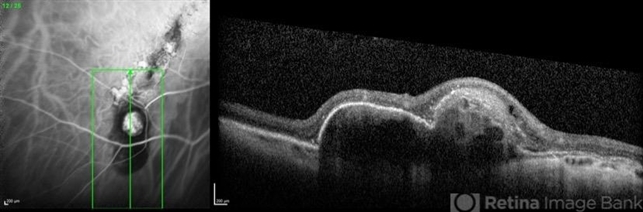

- tilted disc, atrophic pigment epithelium, polypoidal choroidal vasculopathy (PCV), optical coherence tomography (OCT), indocyanine green (ICG) angiography

- Coupled OCT B-scan and ICG angiography of an 81-year-old woman with a tilted disc syndrome complicated with RPE atrophy and polypoidal choroidal vasculopathy.